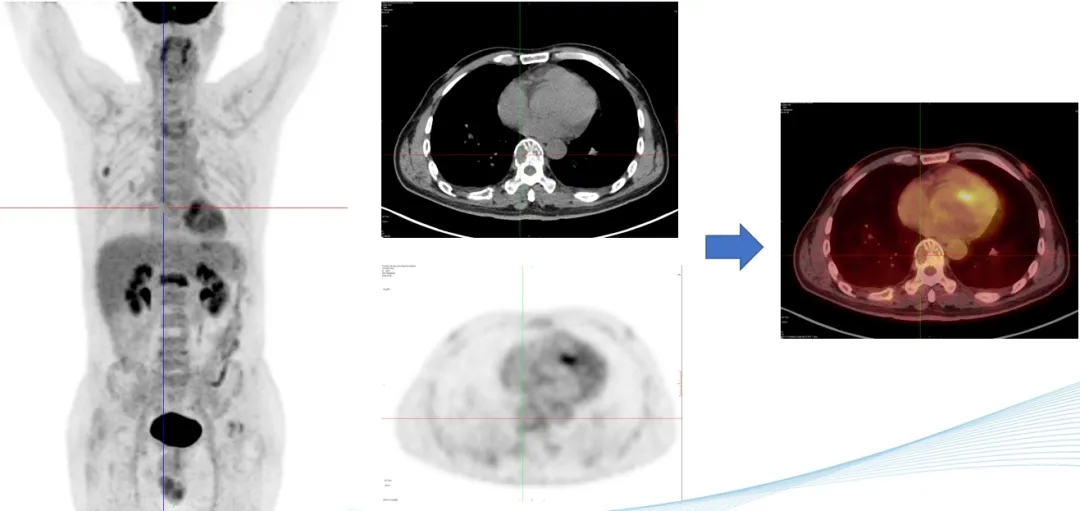

部分PET-CT影像图

前海人寿南宁医院核医学科PET-CT中心的阅片团队对扫描获得的李叔叔的全身影像图片反复多次的观察与比对,凭借着二十几年丰富的阅片经验,核医学科陈伟华主任发现,李叔叔肩胛骨、腰椎多处、双侧髂骨、左侧耻骨等出现了斑点片状、虫蚀样等形态溶骨性骨破坏,考虑恶性病变,多发性骨髓瘤可能性大,建议李叔叔立即进行骨髓穿刺检查。病理学检查结果证实了陈主任的影像诊断。腰痛的罪魁祸首终于找到,目前李叔叔已针对病因进行精准联合化疗。

多发性骨髓瘤(MM)是一种克隆性浆细胞异常增生的恶性疾病,多发于老年人,其发病率居恶性血液病的第二位,目前在我国其发病率呈逐年上升的趋势。PET-CT显像能够在分子水平上提供恶性肿瘤的增殖和代谢情况等信息,并可先于骨质结构变化,在早期发现骨髓的浸润和骨骼代谢的变化,这对于MM骨病的早期诊断具有重要意义。已有的研究结果表明,其在MM的诊断、分期、疗效监测和预后评估等方面具有重要意义。

18F-FDG是一种与葡萄糖结构相似的放射性核素标记化合物,其可进入细胞并滞留在细胞内。当葡萄糖代谢处于平衡状态时,18F-FDG在细胞内的滞留量与细胞消耗的葡萄糖量大体一致,通过18F示踪可反映机体器官、组织和细胞的葡萄糖分布和摄取水平。MM的骨骼和髓外浸润病灶具有高代谢的特点,故在18F-FDG PET-CT显像中显示为高摄取。

PET-CT显像不仅能够直观地显示出MM病灶的代谢情况,而且通过一次检查即可评价全身脏器和骨骼有无浸润,从而多方位、全方面地显示病灶的部位和数量。因此,其对于MM的诊断,特别是对于存在髓外器官受累的患者具有独特的优势。